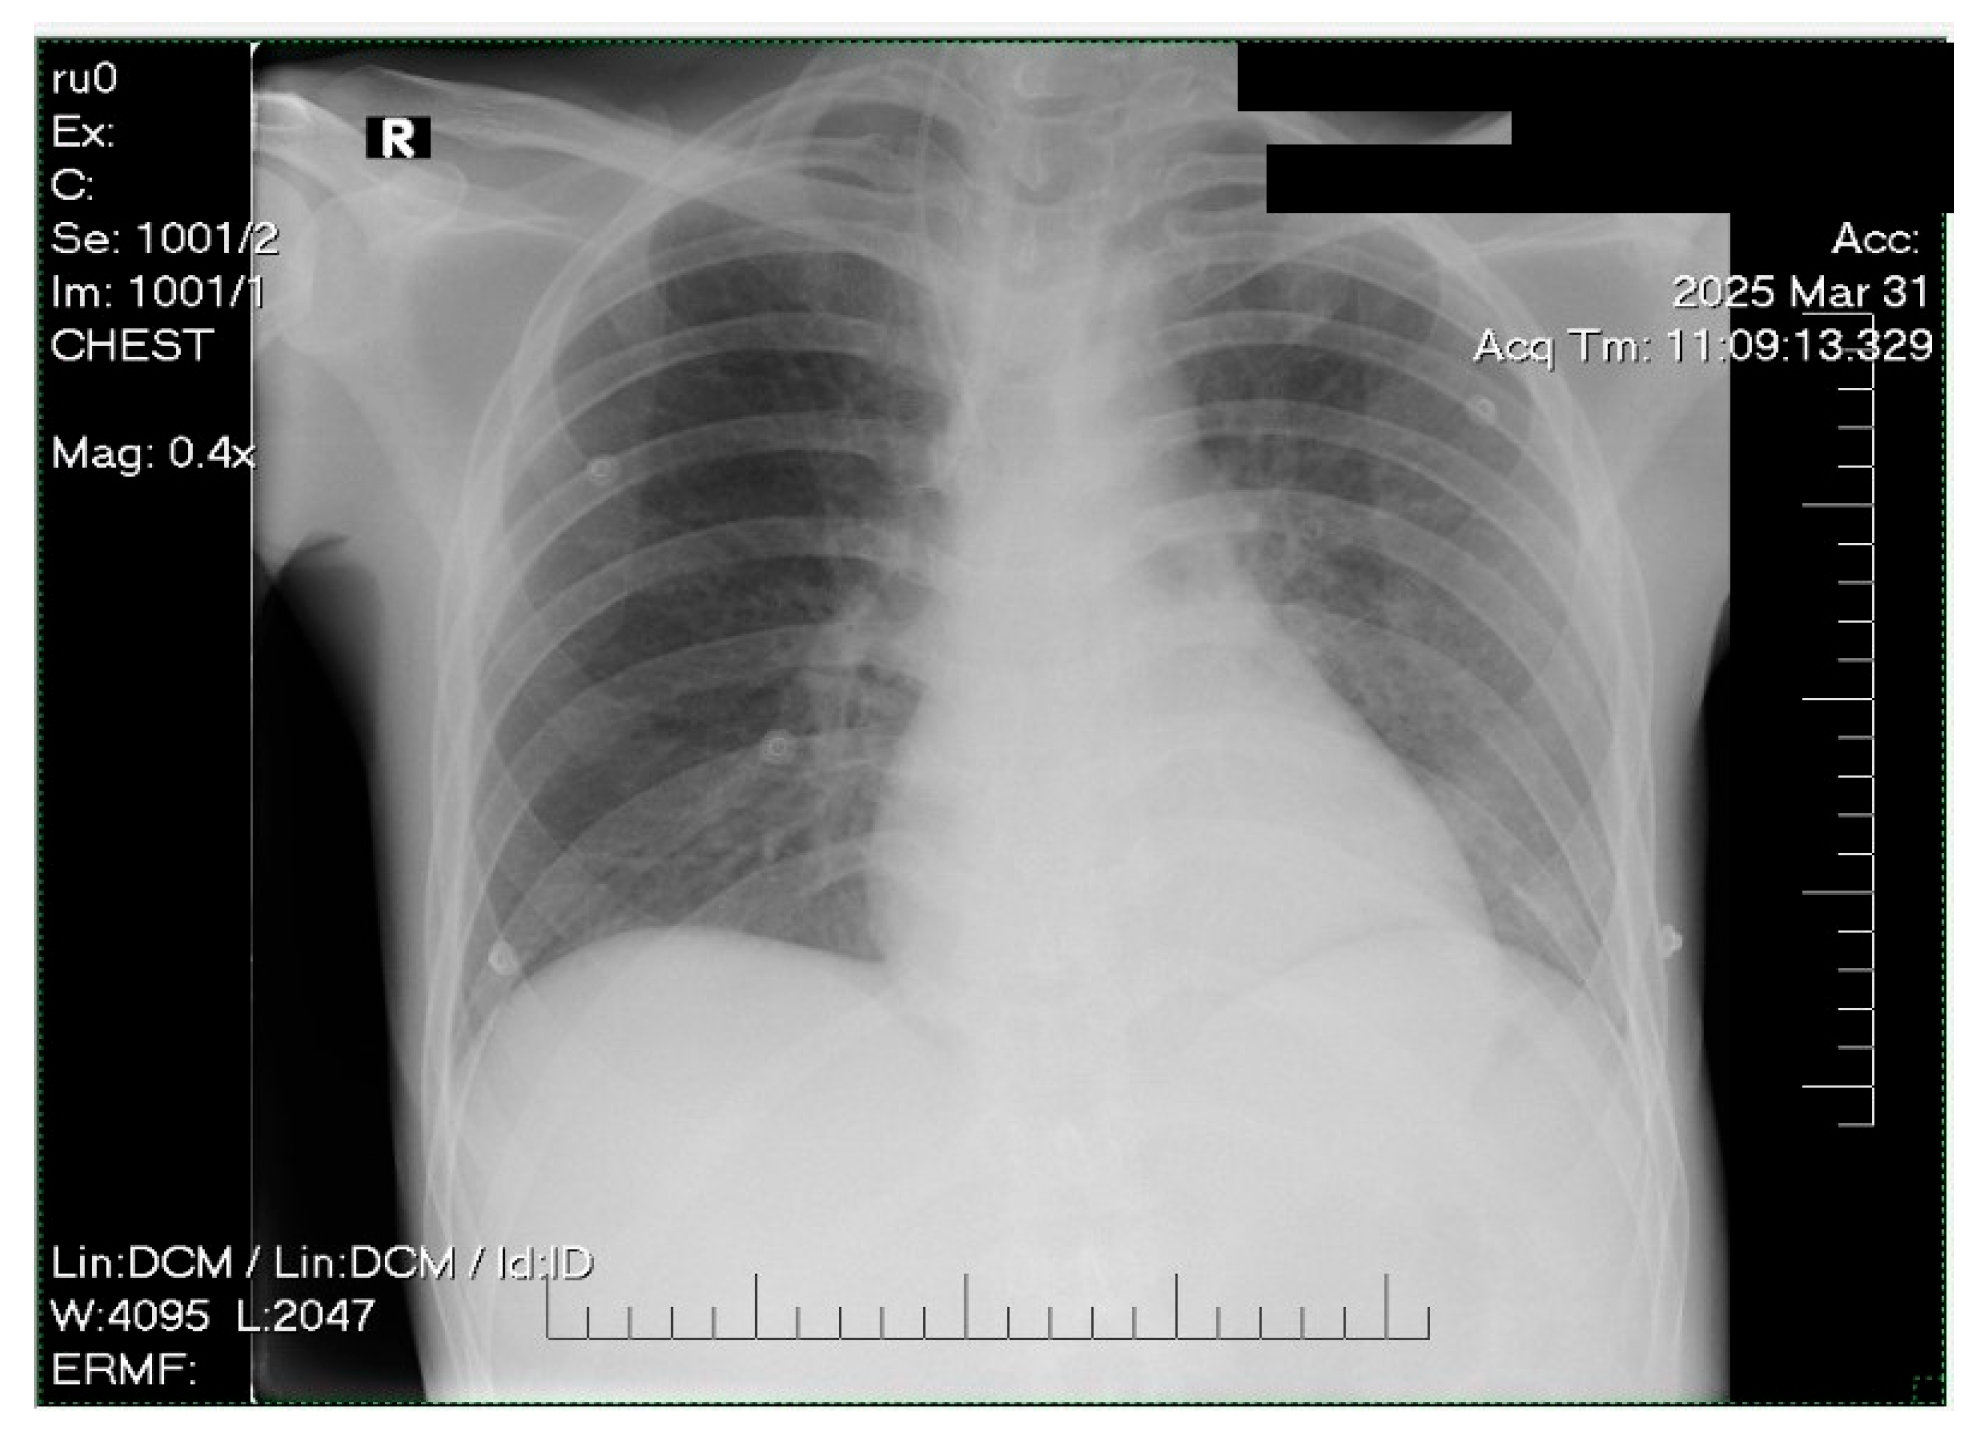

2. Case Presentation